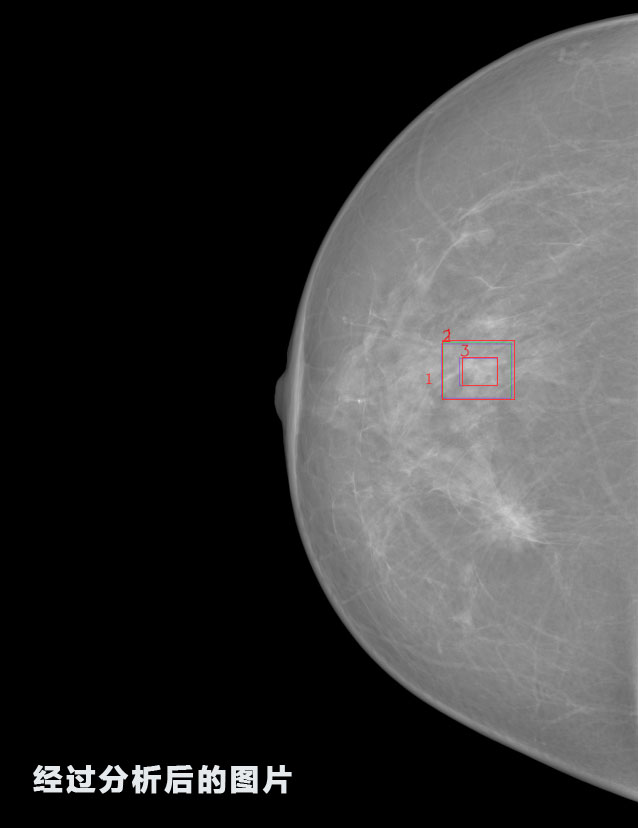

英特健康A(chǔ)I深度學(xué)習(xí)醫(yī)療圖像識(shí)別系統(tǒng)案例_乳腺

識(shí)別報(bào)告:

1.發(fā)現(xiàn)良性鈣化,可能性為19.88%---位置框指數(shù):[1796.0867 1359.8237 2058.1372 1582.5334]

2.發(fā)現(xiàn)惡意鈣化的可能性為15.18%---位置框指數(shù):[1789.4733 1365.9951 2063.7698 1576.0613]

3.發(fā)現(xiàn)惡意鈣化的可能性為12.45%---位于框指數(shù):[1859.3987 1422.3184 2006.5494 1528.2698]